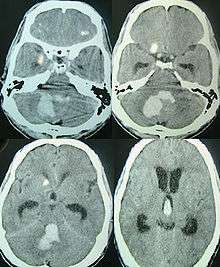

| CT scan of a spontaneous intracerebral bleed, leaking into the lateral ventricles | |

Intraparenchymal hemorrhage can be recognized on CT scans because blood appears brighter than other tissue and is separated from the inner table of the skull by brain tissue. The tissue surrounding a bleed is often less dense than the rest of the brain because of edema, and therefore shows up darker on the CT scan.[14]